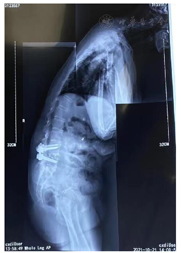

全脊柱全长X线(图1):脊柱骨质增生,脊柱曲度改变,腰椎退行性变,L4、5椎体内固定术后改变。